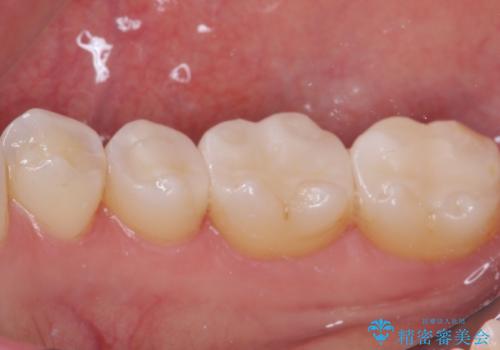

そして次の来院時、セラミックインレーを装着し、噛み合わせなどの調整を行います。

それを左右に分けて行いました。

自然な色調で大変満足されました。